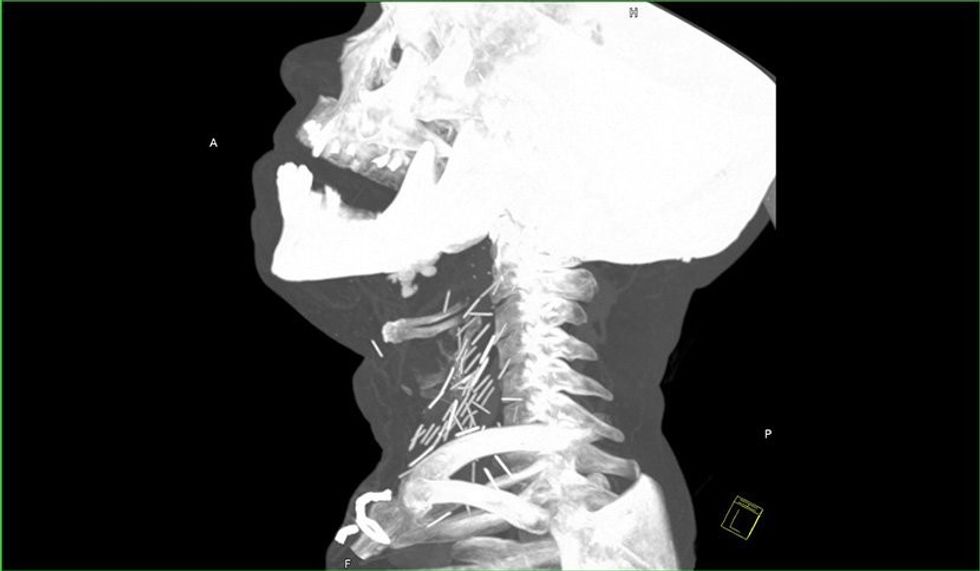

Fotografia e rëntgenit me rreze x ka nxjerr në pah dhjetëra gjilpëra të thyera në qafën e tij, ndërsa pas rekonstruimit të fotografisë në versionin 3D nga radiologët, është konstatuar se vërtetë bëhet fjalë për dhjetëra gjilpëra.

Mjekët besojnë se ky narkoman i cili sipas të gjitha gjasave nuk kishte pasur ku të shpohet në duar, dhe kështu kishte injektuar heroinën në venat e qafës.

Injektimi i heroinës në qafë mund ta lë pavetëdije narkomanin për disa sekonda, ku si pasojë gjilpëra mund të thyhet dhe një pjesë e saj të mbetet në qafën e tij.